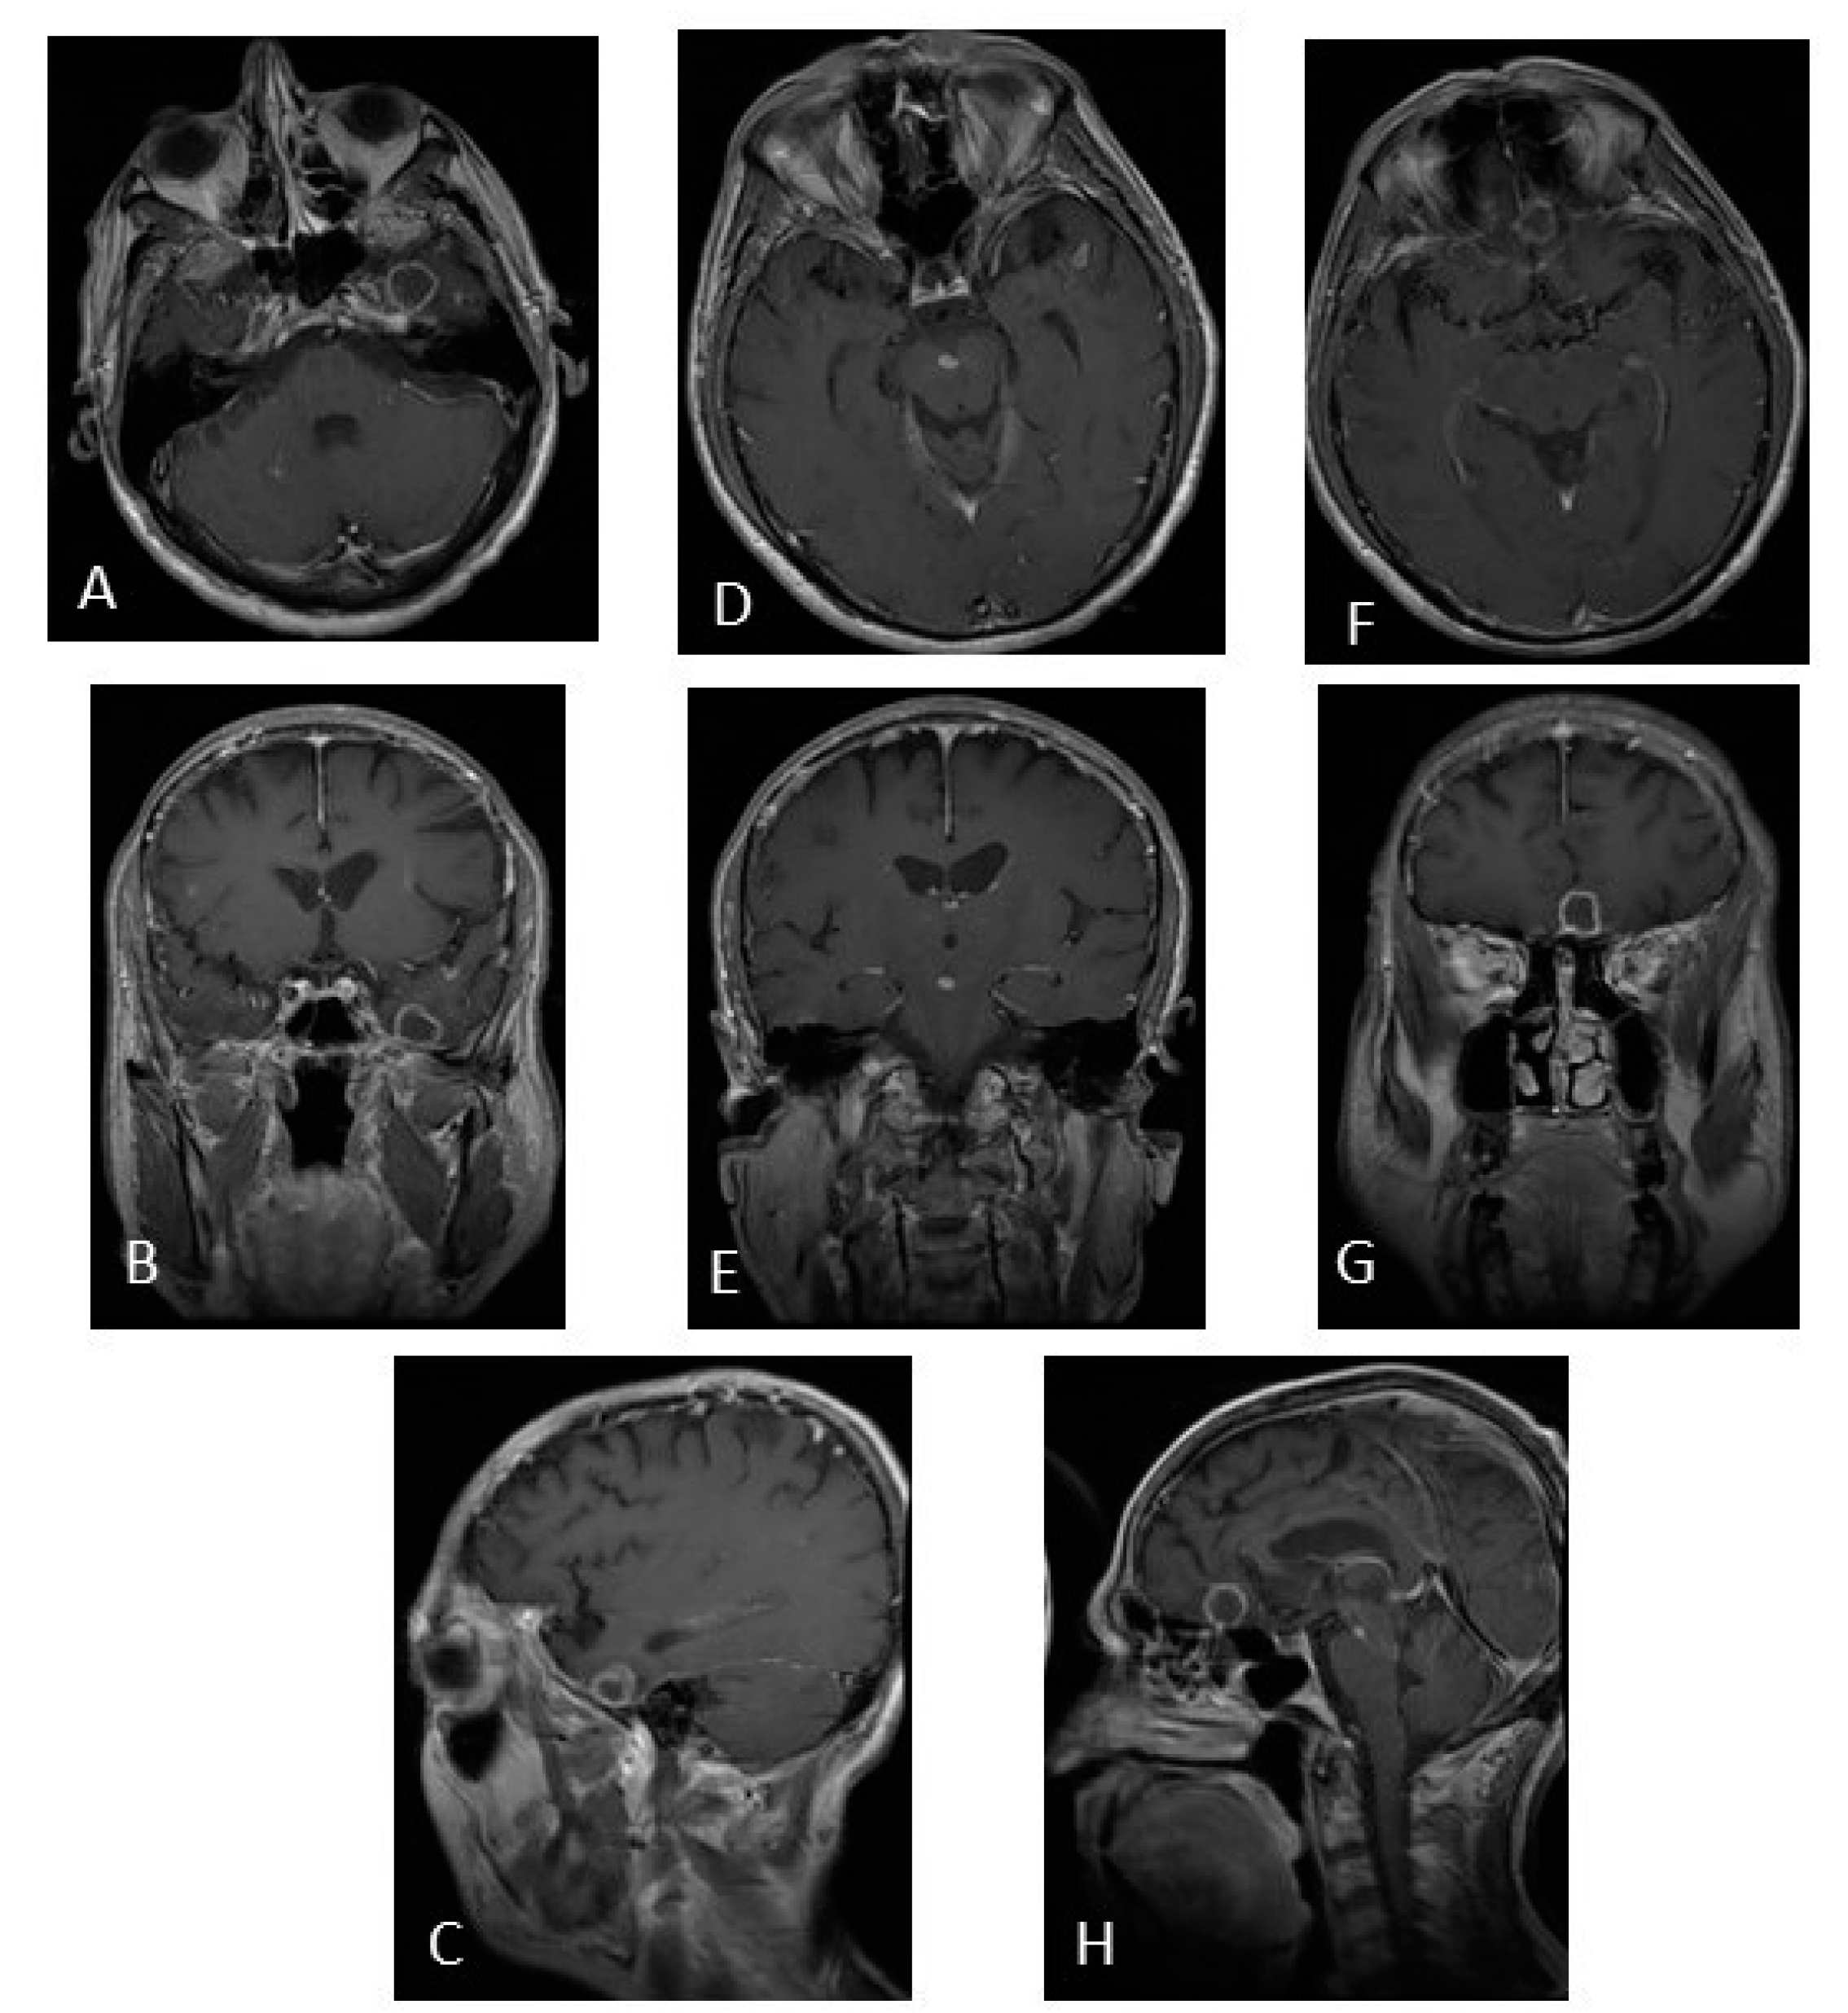

3.2. Intracranial Neurotuberculosis

4.2. Intracranial NeuroTB